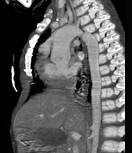

问题 患者,男性,8岁,发绀、气促,易感冒,彩超提示只见一个心室,CT检查如图所示,请选择正确的选项 ( )

选项 A、考虑三尖瓣狭窄 B、右前斜位示左心房增大,心后上缘后突压迫冲钡食管 C、左前斜位示心影向后下方突出 D、考虑二尖瓣狭窄

答案 BCD